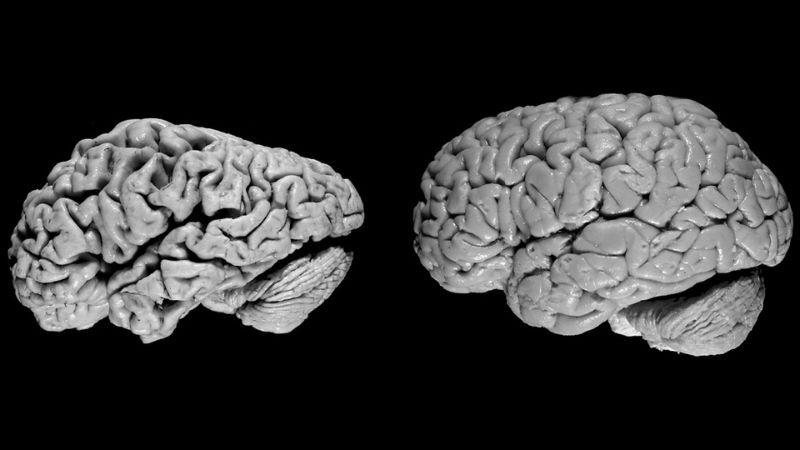

Trước khi tìm hiểu bệnh Alzheimer được chẩn đoán thế nào, cùng tìm hiểu về nguyên nhân gây bệnh. Bệnh Alzheimer được đặc trưng bởi sự xuất hiện của các mảng amyloid beta bên ngoài tế bào và các đám rối tơ thần kinh bên trong tế bào, gây suy giảm chức năng và làm chết tế bào thần kinh theo chương trình. Nghiên cứu dọc theo dõi những người khỏe mạnh chuyển sang giai đoạn Alzheimer cho thấy sự thoái hóa thần kinh này có thể bắt đầu từ 20 - 30 năm trước khi các triệu chứng lâm sàng trở nên rõ ràng. Tuy nhiên, mật độ và vị trí của các mảng amyloid không tương quan với triệu chứng hoặc mức độ nghiêm trọng của bệnh Alzheimer. Các nghiên cứu giải phẫu học cho thấy những thay đổi bệnh lý lan rộng khắp vỏ não và các cấu trúc xung quanh, đặc biệt là vùng đồi thị. Trong một số trường hợp, bệnh Alzheimer có tính chất di truyền với gen trội. Gia đình có bệnh nhân Alzheimer cũng thường thấy nhiều trường hợp mắc hội chứng Down.

Bệnh Alzheimer là hậu quả của sự thoái hóa các tế bào não, có thể được biểu hiện qua hình ảnh chụp chiếu não bộ. Vậy hình ảnh của bệnh Alzheimer được chẩn đoán thế nào? Các kỹ thuật chẩn đoán hình ảnh phổ biến bao gồm: